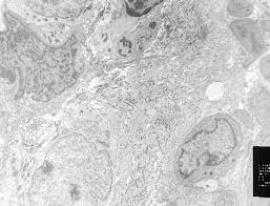

Верификация саркомы проводится путем ее морфологического исследования под микроскопом. Для этого берется материал опухоли, удаленной во время операции, если ее размер менее 2 см. В остальных случаях либо же проводится специальная процедура – биопсия, во время которой из новообразования с помощью специального инструмента забирается столбик ткани. В ряде случаев требуется не только морфологическое исследование, но и более детальное изучение опухоли, например, исследуется наличие определенных генетических поломок или ее рецепторный статус. Такие данные могут помощь при выборе тактики лечения.